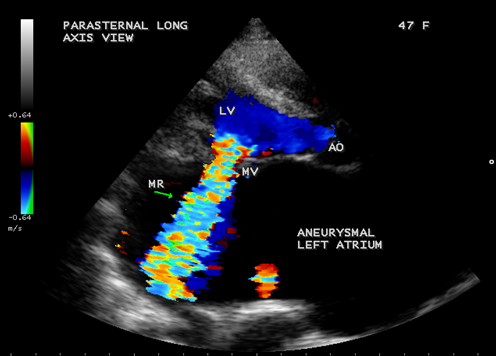

Case 4. Giant left atrium in mixed rheumatic mitral valve disease- both mitral stenosis and regurgitation as shown in Figures 15 to 20 in a 47-year-old female. The patient was advised lifelong penicillin prophylaxis, MVR (mitral valve replacement), LA volume reduction surgery with Cox-Maze procedure for atrial fibrillation.

Figure 19. Parasternal long axis view showing the severe mitral regurgitation and giant left atrium in a 47-year-old female.

Figure 20. Parasternal long axis view showing the mitral stenosis jet and giant left atrium in a 47-year-old female.

The balloon-like enlargement of the left atrium which occupied the whole of the posterior, right and left mediastinum and the rest of the heart looks like a ‘crown on a cushion’ as shown in Figures 17 and 18 in mixed mitral valve disease (both stenosis and regurgitation) as in Figures 19 and 20.